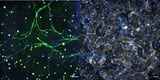

This lymph node-on-a-chip model mimics dynamic fluid flow and cellular interactions, allowing scientists to study immune behavior outside the human body.

Published in April 2025 in APL Bioengineering, the model accurately replicates the crucial functions of natural lymph nodes, particularly the dynamic fluid flow essential for immune function.

The study revealed that inflammation significantly alters fluid flow in lymph nodes, affecting the behavior of immune cells, particularly T cells, which underscores the importance of fluid dynamics in immune studies.